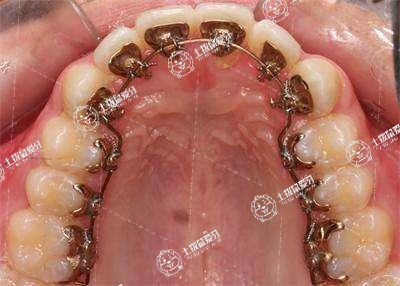

地包天臨床上是指反頜,是指下前牙咬在上前牙的外面,可以通過地包天矯正術或者佩戴牙套進行改善,手術主要是通過截骨并前移后縮的骨組織。佩戴牙套主要是結合牙齒生長的方向,設計矯正方法。

如果地包天不是特別的嚴重,則可以通過佩戴牙套進行矯正。但如果比較嚴重,佩戴牙套效果不是特別理想,則可以采取手術的方法矯正。

在進行牙齒,對于輕度的一些中度骨性畸形的成人患者,多采用牙齒帶廠的方法進行矯治,而對于重度骨性畸形的成人患者,只能采用外科手術和正畸聯合的方法進行矯治。